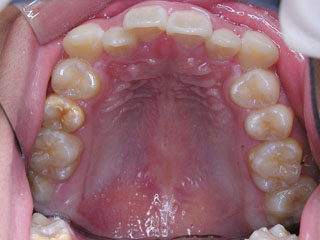

主訴:上顎前歯の突出 口が閉じにくい

診断名:叢生と伴う上顎前突

年齢:13歳

使用した主な装置名:TPB、HG、マルチブラケット装置

抜歯/非抜歯および抜歯部位:抜歯(上顎左右第一小臼歯)

治療期間:動的処置2年6か月、経過観察3年6ヶ月

費用の目安:90~140万円

リスク、副作用:抜歯によるリスク、マルチブラケット治療に伴う歯根吸収など偶発症が発生するリスクがある。

上顎前歯の前突が見られます。下の歯には中程度の叢生と口唇前突感がみられました。分析結果では、2級1類と呼ばれるタイプの不正咬合でした。上顎の左右第一小臼歯を抜歯してマルチブラケット治療を行いました。